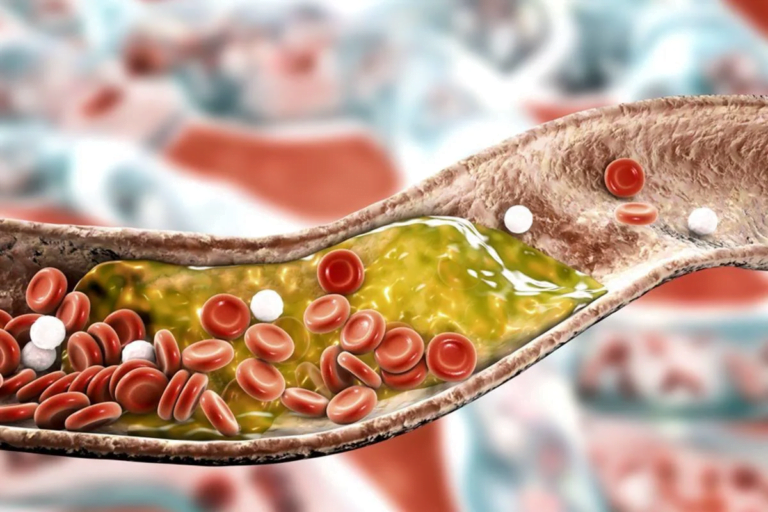

O fígado é um dos órgãos mais importantes do nosso corpo, desempenhando funções cruciais para a nossa saúde. Infelizmente, a má alimentação e o consumo excessivo de bebida alcoólica foram levados cada vez mais pessoas a serem diagnosticados com a…